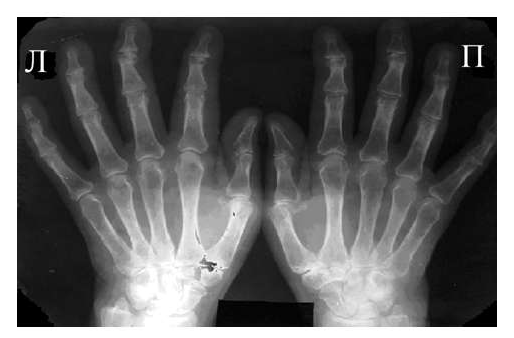

Одним из главных отличительных признаков ревматоидного артрита (РА) от других заболеваний является симметричность изменений мелких суставах кистей и стоп, которые становятся суставами-«мишенями» в первую очередь и поэтому именно эти области изучаются для определения стадии заболевания. Наиболее часто используемой в повседневной практике рентгенологической классификацией является деление ревматоидного артрита на стадии по Steinbrocker в различных модификациях.

Основными рентгенологическими симптомами РА являются следующие: остеопороз, кистовидные просветления костной ткани (кисты), сужение суставной щели, эрозии суставов, костные анкилозы, деформации костей, остеолиз, вывихи, подвывихи и сгибательные контрактуры суставов. Рентгенологическая диагностика развернутых стадий РА, исходя из нашей практики, как правило, затруднений не вызывают.

Рис. 3 Сочетание ревматоидного артрита и остеоартроза

Большинство ошибок встречаются при начальных стадиях, особенно при начале РА в пожилом возрасте и сочетании его с остеоартрозом (см. рис. 3). В этом случае для подтверждения диагноза РА и предупреждению случаев его гипердиагностики служит выявление симметричных эрозий в типичных для ревматоидного артрита суставах (запястья, плюснефаланговые, пястно-фаланговые).

Рис. 4. Изменения кистей при ревматоидном артрите (а остеопороз, бсужение суставных щелей, в кистовидные просветвления, г костные эрозии, д анкилозирование)

Необходимо также помнить, что, как правило, при РА эрозии не предшествуют околосуставному остеопорозу, кистам и сужению суставных щелей. Имеет место последовательность развития стадий РА (см. рис. 4), в отличие от эрозивных артритов другого генеза (псориатического, серонегативного)

Костные анкилозы выявляются только в суставах запястий и во 2-5-м запястно-пястном суставах, редко в лучезапястных и суставах предплюсны. Никогда анкилозы не формируются в межфаланговых суставах кистей и стоп, в первых запястно-пястных и плюснефаланговых суставах. Анализируя сроки появления основных рентгенологических проявлений наиболее типичным по нашим данным и по данным других авторов [LandeweR.] является появление первых симптомов РА (околосуставного остеопороза и кистовидных просветлений) через несколько месяцев (до года) от начала заболевания, эрозии выявляют на 2-3 год от начала заболевания.